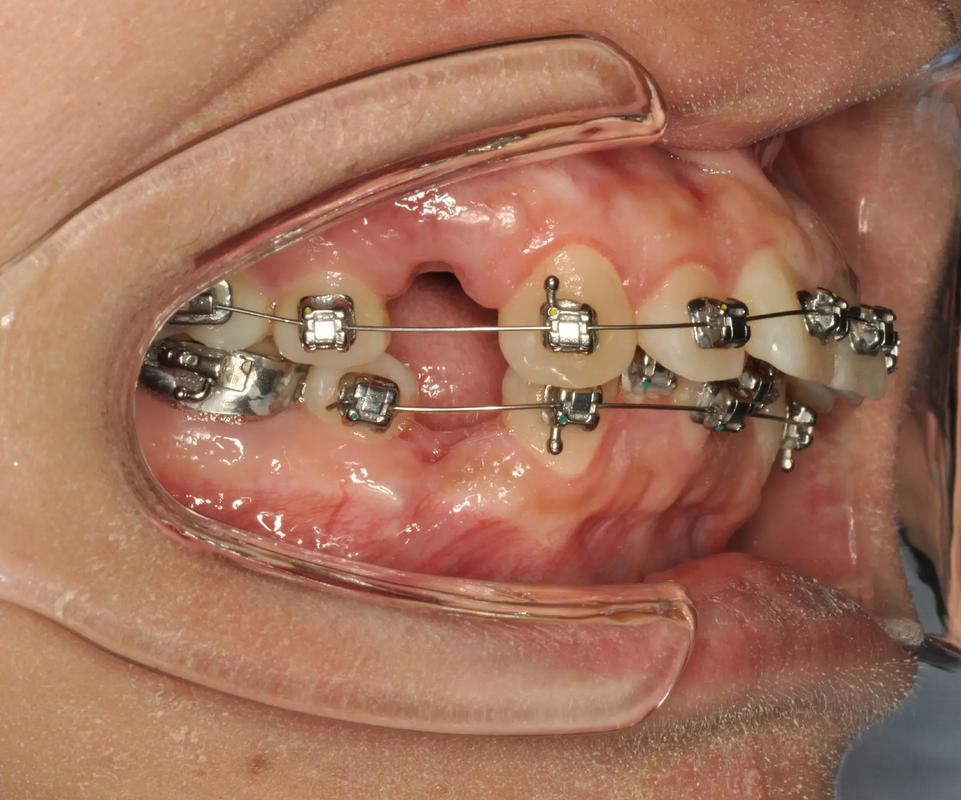

以临床常见的“普通带环+颊管”结构为例(参考口内正面/侧面图片):

- 环体部分:带环的金属环体呈环形,内壁涂有粘接剂(如玻璃离子水门汀),紧密包裹磨牙牙冠的颊侧、舌侧及(牙合)面(咬合面),边缘位于牙龈上方约1mm,避免压迫牙龈(图片中可见带环与牙龈之间无明显缝隙,说明贴合紧密)。

- 颊管结构:在带环的颊侧(靠近脸颊的一侧),焊接有一根金属管,称为颊管,颊管的内径与矫治弓丝的直径匹配(如0.022英寸×0.028英寸的方丝),弓丝插入颊管后,可沿颊管滑动,传递矫治力(图片中可见插入颊管的银白色弓丝,带环与弓丝之间无明显晃动)。

- 粘接界面:带环与牙齿的接触区域(图片中带环内壁与牙冠的交界处)可见淡黄色的粘接剂,边缘光滑连续,无气泡或裂隙,确保带环在治疗期间不脱落。